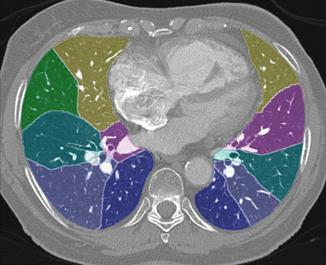

Quantificazione dell'enfisema mediante TC e software MeVisPulmo

Le TC sono state esaminate mediante l'impiego di un software (MeVisPulmo, Bremen) che consente la misurazione totale del volume polmonare, la densità media, i pixel, il "bulla index" e l'analisi sia qualitativa che quantitativa dell'enfisema polmonare. La valutazione prevede la segmentazione delle vie aeree e del polmone. I dati processati vengono storati come immagini DICOM (Digital Imaging and Communications in Medicine). Alla fine della processazione dei dati i valori vengono visualizzati e trascritti in un report. Le regioni lobari vengono indicate con differenti colori nelle sezioni sagittali, coronali e assiali come indicato nella fig. 3-5.

Figura 5. Immagine assiale con ripartizione dei segmenti

polmonari indicati con colori diversi.